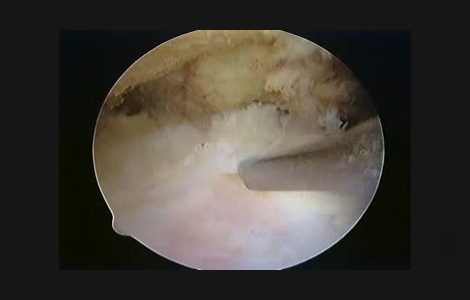

断裂していない腱板を関節鏡で滑液包側からみると

断裂した腱板を関節鏡でみると

関節鏡視手術